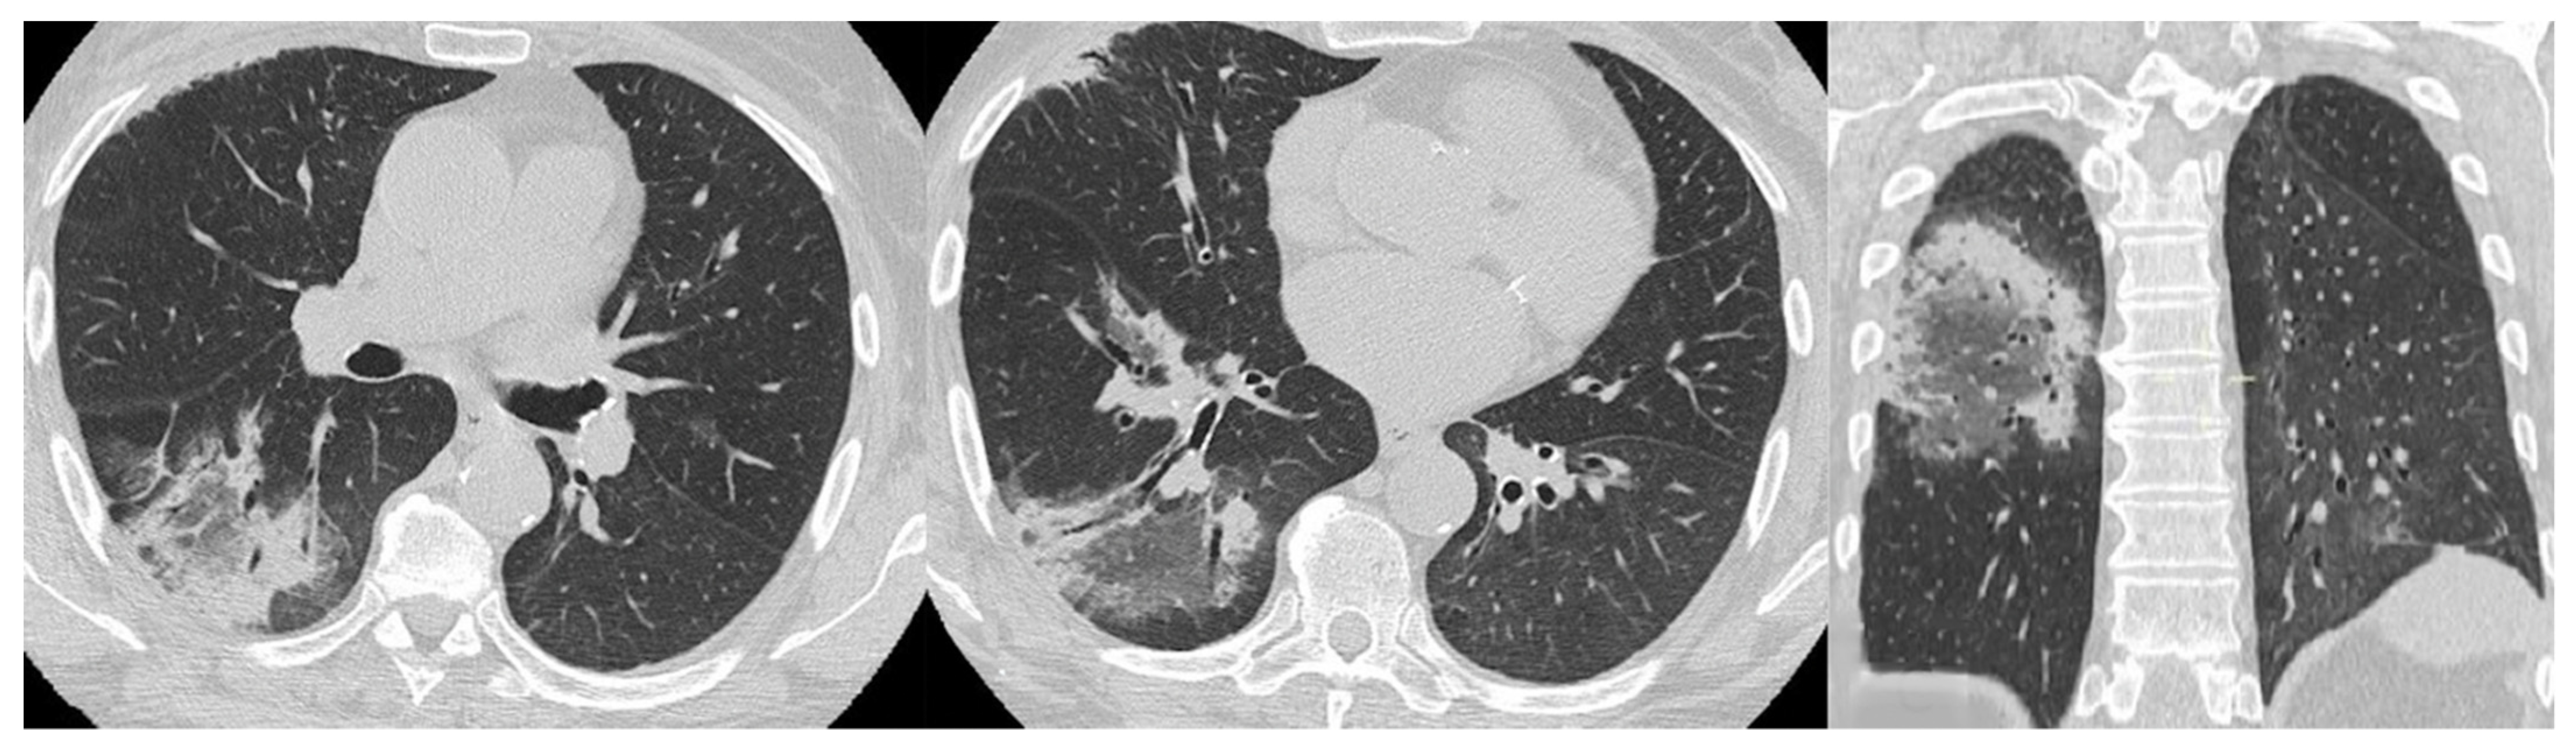

Acute Type

- Acute or rapidly progressive ILD (acute interstitial pneumonia and radiological evidence of acute respiratory distress syndrome (ARDS) due to diffuse alveolar damage) [44];